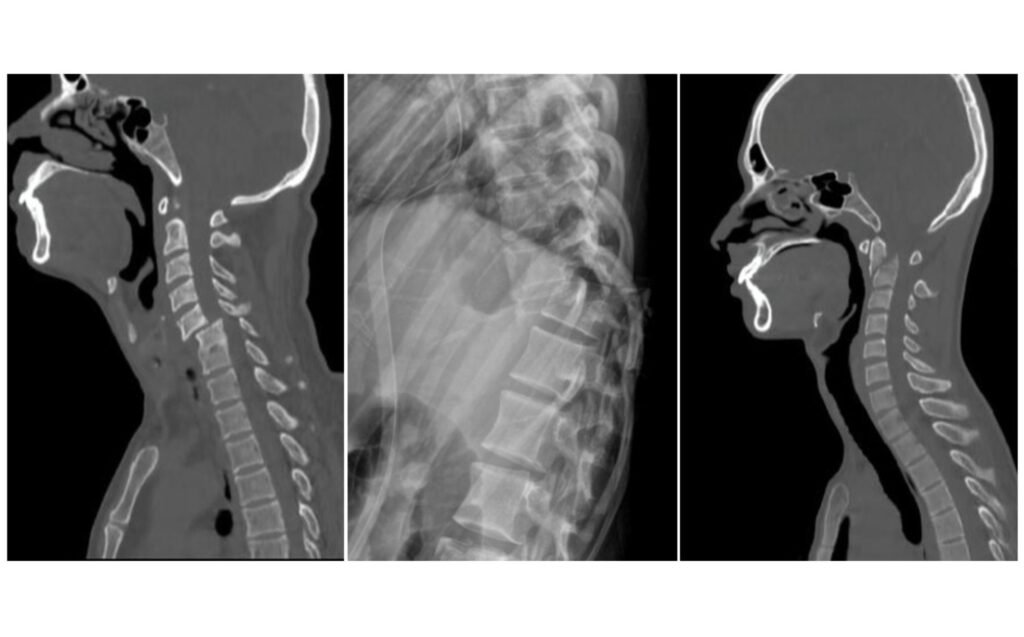

Spinal Fractures

Spinal fractures commonly occurs at thoracolumbar and cervical region, usually following falls, road accidents, or high-impact injuries. These fractures can cause severe neck or back pain, limited movement, and, in some cases, pressure on the spinal cord or nerves resulting paralysis of all limbs. Evaluation includes X-rays, CT, and MRI to determine stability and the need for intervention. Treatment ranges from bracing and rest for stable fractures to minimally invasive or open surgery for unstable injuries. The goal is to restore spinal stability, prevent nerve damage, and help patients return safely to normal activity.